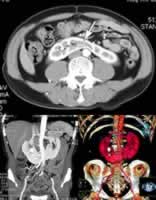

患者男,58岁,反复肉眼血尿伴腰痛2年余,腹中部触诊可及包块。

图1 肾下极水平增强CT扫描,可见双侧肾脏于脊柱前融合(箭号),右侧肾下盏内可见致密结石。

图2 最大密度投影(MIP)。

图3 容积再现(VR)示双侧肾下极于中线融合(马蹄肾畸形),双侧肾门朝向内上,右肾盂内多发X线阳性结石。